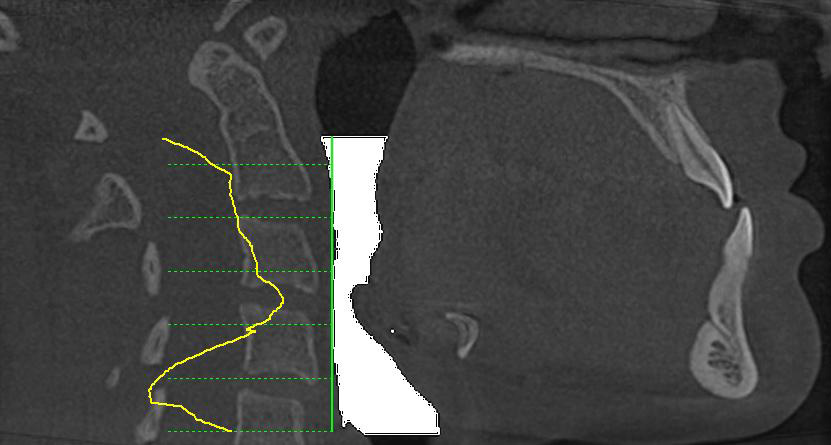

Клінічний діагноз: вертикальний тип росту, скелетний клас III, асиметричний за рахунок зміщення нижньої щелепи вправо. Зубо-альвеолярне співвідношення по класу III, набута втрата зубів 36,46, скупченість фронтальної групи зубів обох щелеп.

Мал.1. 3D реконструкція кісток лицьового черепа. 3D цефалометрія

Мал.2. Аналіз дихальних шляхів показав мікрогнатію (недорозвинення верхньої щелепи) і пов’язане з нею ретроположення язика, що призвело до зниження обсягу дихальних шляхів на рівні ротоглотки.